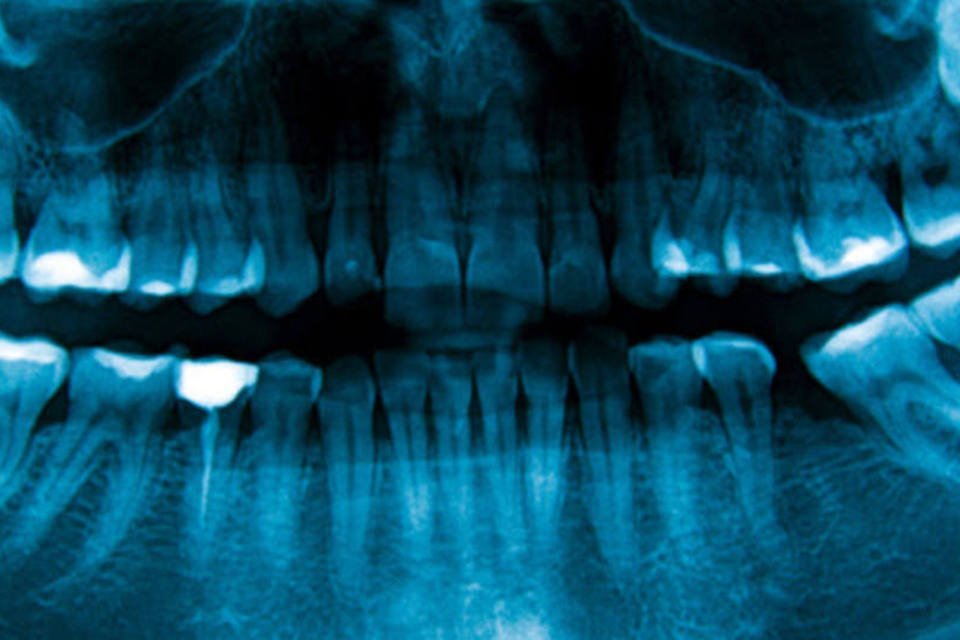

Odontologia: scanner lê e digitaliza imagens de raios X obtidas por meio de placas constituídas por sais de terras raras, entre outros materiais (Getty Images)

O scanner lê e digitaliza imagens de raios X obtidas por meio de placas constituídas por sais de terras raras, entre outros materiais. Ao incidir raios X sobre essas placas, as cargas eletrônicas das moléculas das substâncias que compõem o material são excitadas e entram em um estado energético chamado metaestável (diferente de seu estado de equilíbrio).

O scanner lê e encaminha quase em tempo real a imagem gerada pela placa para um monitor de alta resolução – semelhante aos utilizados em exames de ultrassonografia. Um software específico processa e gera a radiografia com altíssima resolução, que pode ser armazenada ou enviada pela internet.